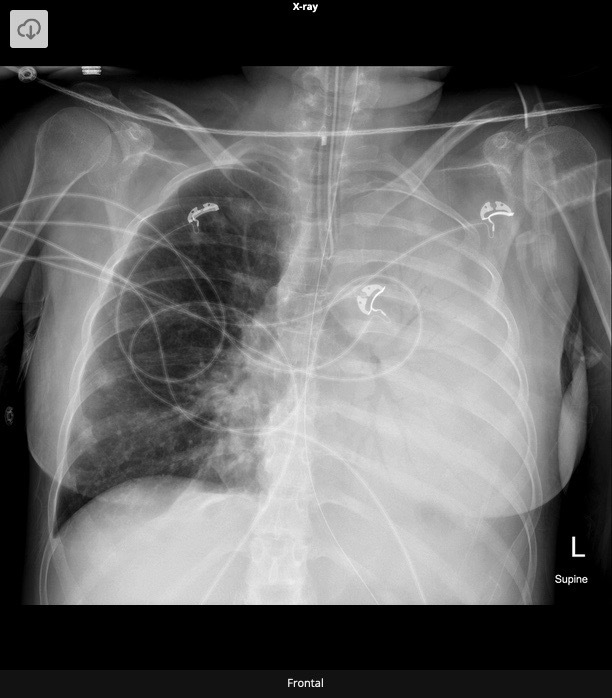

20.1 A 15-year-old boy undergoes a cardiac procedure for congenital heart disease. The intrathoracic device is a(n) (chest X-Ray shown)

a) AV repair

b) PV repair

c) ASD closure device

d) Parachute device

e) Right atrial appendage closure

device

Amplatzer Device